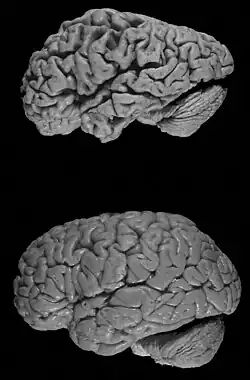

Frontotemporal dementia

Frontotemporal dementia is associated with damage to the Frontal and Temporal lobes of the brain, and is unlike the damage that causes Alzheimer’s disease (Johns et al., 2009). The Temporal Lobe is associated with processing sensory input, visual memories, understanding language, emotion, meaning and storing new memories, whereas the Frontal lobe contains dopamine sensitive neurons and is associated with short-term memory, planning and motivation. As well as the other types of dementia, Frontotemporal dementia is categorised by an impairment in one’s memory and daily activities, but also involves early discrepancies with social and interpersonal behaviour (Johns et al., 2009).